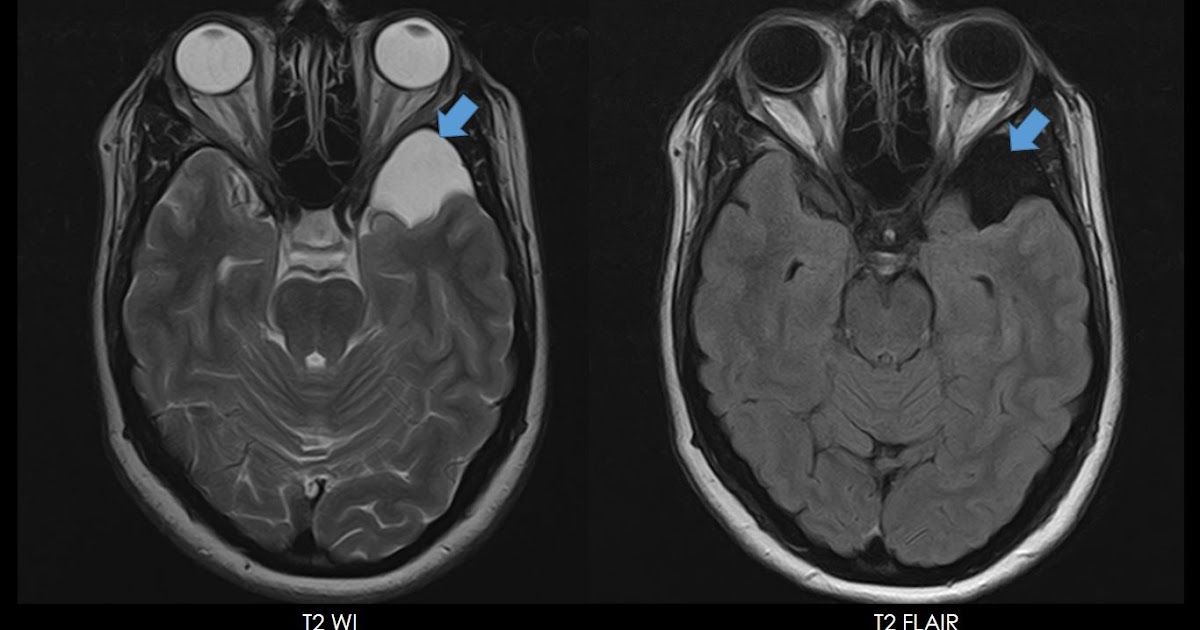

Ultimate Radiology Intracranial Arachnoid Cyst Galassi Type I Porencephalic Cyst Vs Arachnoid Cyst They affect people of all ages, but they arise in babies and children. One of the main differential diagnoses is a porencephalic cyst, which communicates with the lateral ventricle or. The fluid consists of cerebrospinal fluid (csf). Porencephaly is a very rare disorder that affects your central nervous system. Arachnoid cysts are the most common kind of brain cyst. It. Porencephalic Cyst Vs Arachnoid Cyst.